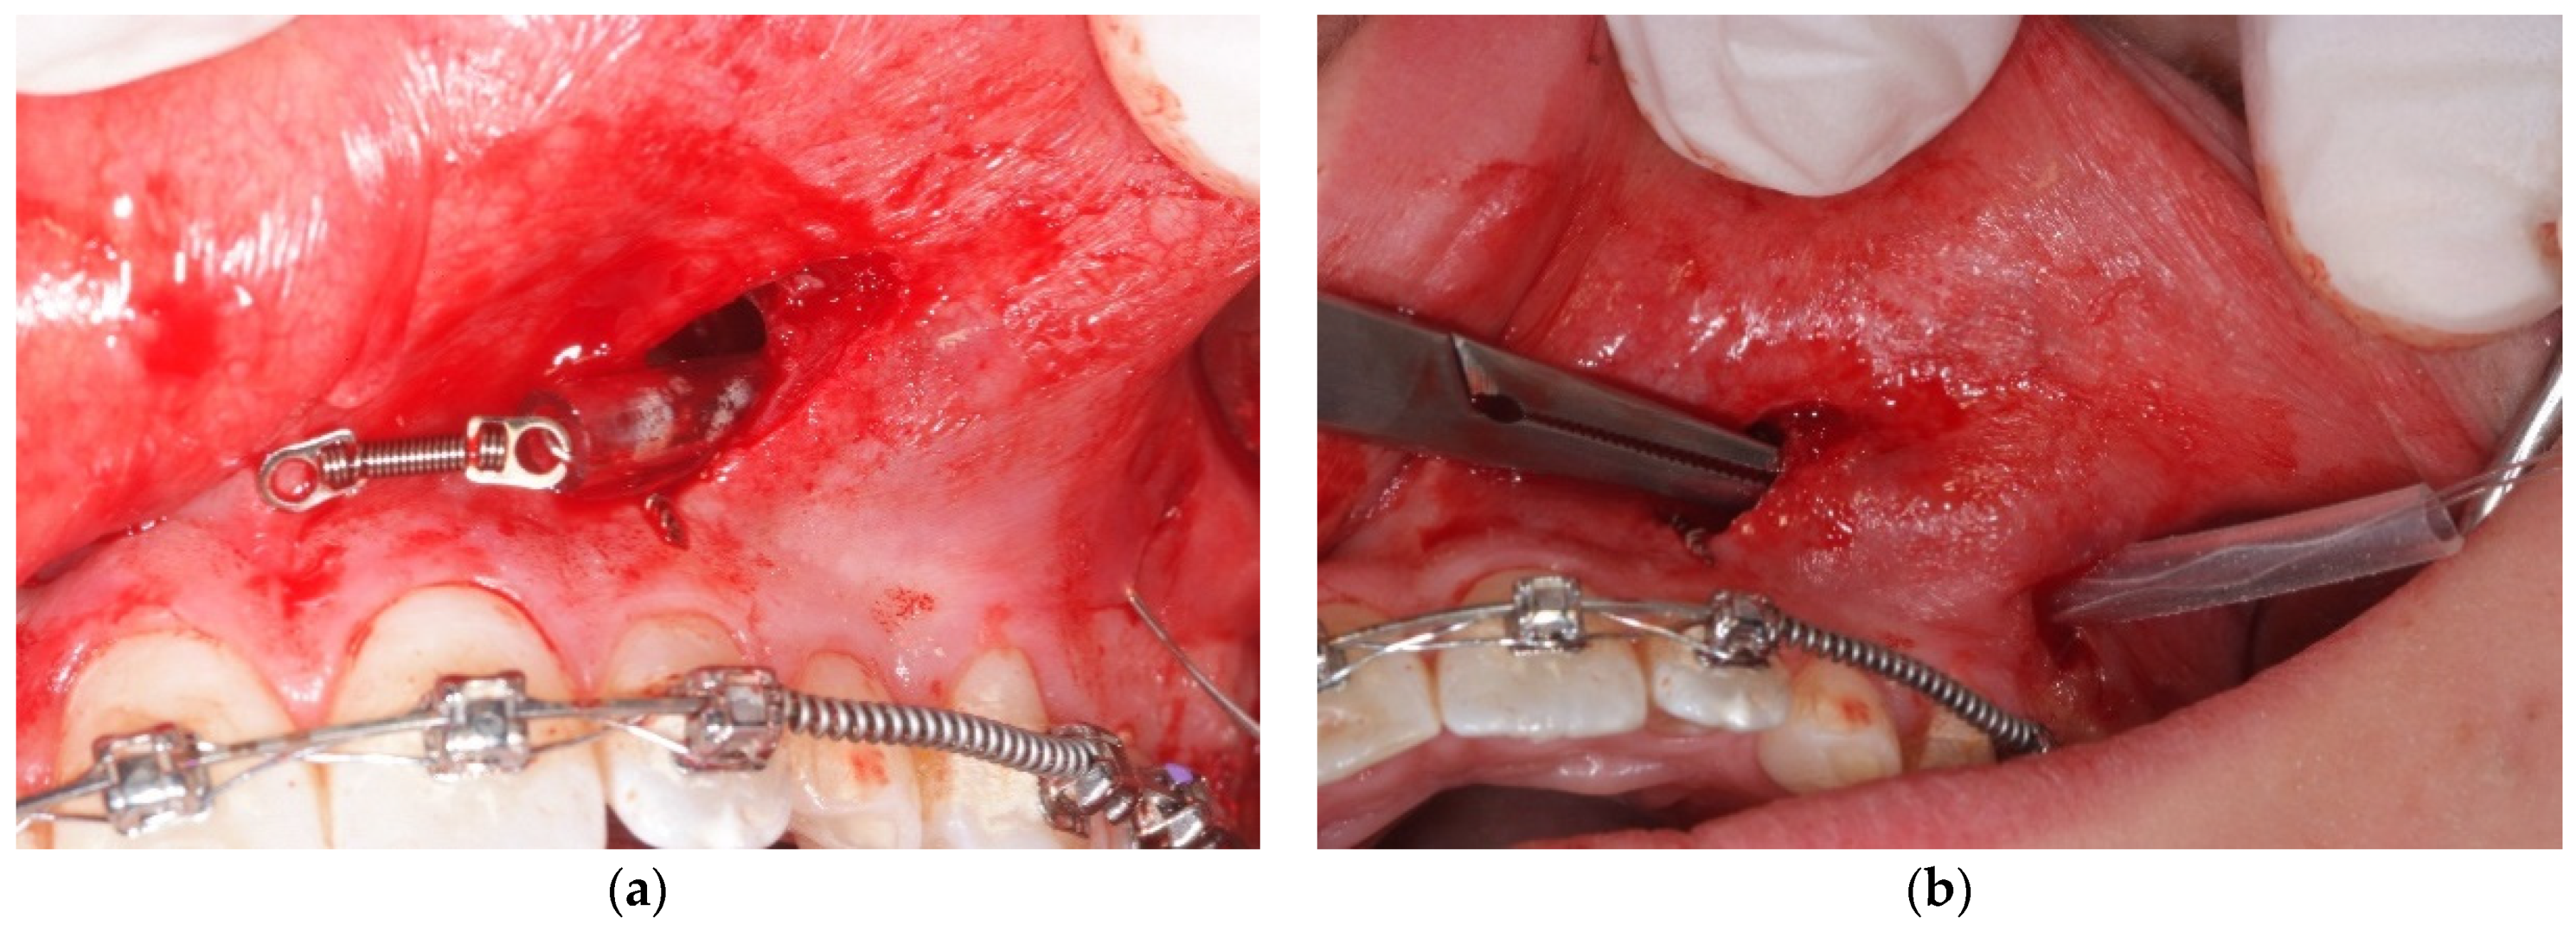

- A first vertical incision, at the level of the impacted tooth crown, and its exposure, with a periosteal elevator, are then performed. If a bony cortex is present overlying the crown, a small bony cavity is made using the multi-blade conical burr with a low-speed right-angle handpiece to expose all of the canine’s crown surface (Figure 3). In any case, a thin groove must be present peripherally to the canine’s crown to guarantee a good isolation from bleeding. Moreover, a further ostectomy is performed on the tooth side toward which the orthodontic traction will be performed (traction route);

- A second vertical incision is made between the first and second premolar, and the sub-periosteal tunnel is created with a periosteal elevator to connect the two incisions from front to back (Figure 4);

- After a good hemostasis is reached, the button is attached to the buccal canine crown’s surface, following all necessary steps including enamel etching with 37% orthophosphoric acid for 30 s and applying adhesive. Therefore, the button is connected by means of a metal ligature to a 150 gr closed coil spring (NiTi). At the distal end of the NiTi coil, another metal ligature is inserted to facilitate the passage of the traction system under the subperiosteal tunnel (Figure 5);

- Then, the second metallic ligature is inserted in the subperiosteal tunnel to leak out from the posterior vertical incision. Alternatively, the Klemmer forceps can be inserted through the posterior vertical incision and pushed forward inside the tunnel until its end is visible from the anterior incision, to take the spring end and train it posteriorly until it exits from the rear end of the tunnel;